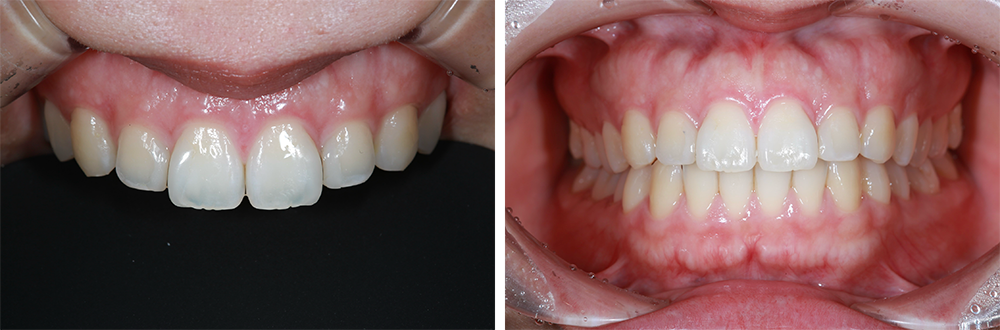

症例4

前歯の形・色の改善を目的として矯正治療とセラミック治療を行った症例(30代女性)

治療中

症例4 治療中

治療後

症例4 治療後

症例4 治療後2

治療の流れ

矯正治療 → 歯の形成 → 仮歯装着 → セラミック装着

使用材料

ジルコニアクラウン

治療期間

例:約1年

治療結果

矯正治療により、歯の位置関係が良くなり歯を削る量を最小限にセラミック治療ができました。

見た目だけでなく、機能面も回復し長期に安定する治療となりました。

費用

• 矯正治療(上顎のみ) 330,000円(税込)

• ジルコニアクラウン(奥歯)93,500円(税込)×5本=467,000円(税込)

• ジルコニアクラウン(前歯)110,000円(税込)×6本=660,000円(税込)

※保険適用外の自由診療です。